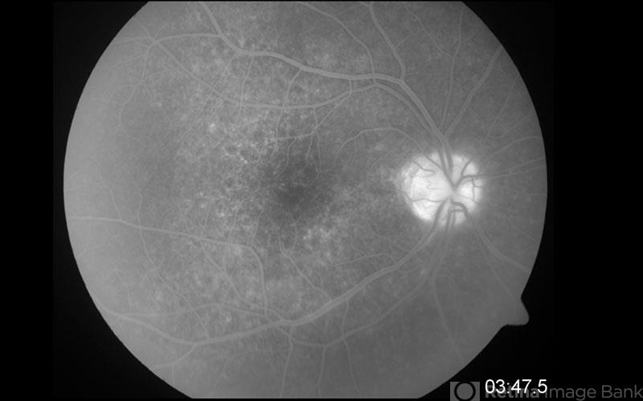

- Acute Syphilitic Posterior Placoid Chorioretinitis

- acute syphilitic posterior placoid chorioretinitis, syphilis

- Fluorescein angiogram of a 42 year-old male, showing hyperflourescence with a granular pattern in the posterior pole.